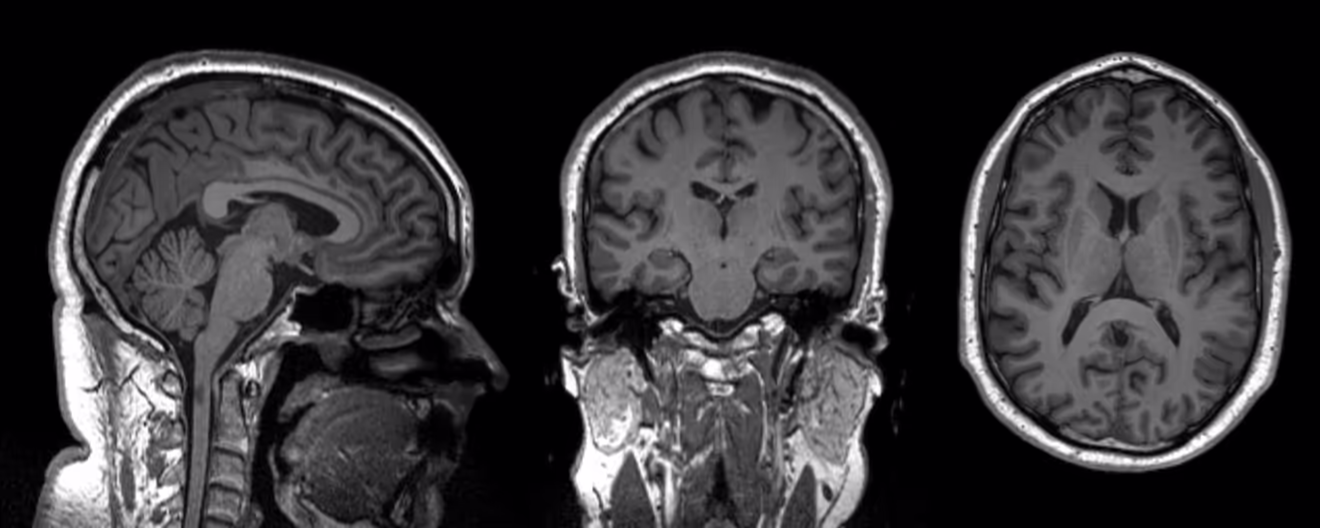

MRIs and my brain on drugs

Part of my MS also means I have yearly MRIs, but this year my consultant asked if I would be willing to partake in a study in to fatigue and MS, in exchange for £50 and imaging data of my brain. Oh - photos of my brain - yes please!

Short version, here's my brain: